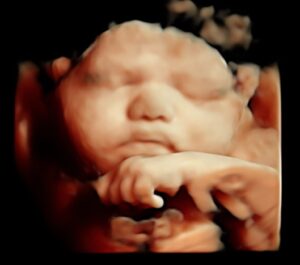

C’est la meilleure période pour réaliser une échographie plaisir en 4D ! Vous allez pouvoir observer les traits et les premiers mouvements de votre bébé. Durant ces semaines, il est même possible de l’observer cligner des yeux. Pendant cette période de développement très rapide, de nombreux parents réalisent plusieurs séances afin de suivre cette évolution.

La meilleure période pour venir faire une échographie 4D est à partir de la 22ème semaine de grossesse. C’est à ce moment-là que l’on distingue une vue d'ensemble du bébé, ses gestes... En se rapprochant de la 32ème semaine de grossesse, les traits et le visage de votre bébé se dévoilent plus précisément !

Notre Galerie.

Découvrez notre galerie vous présentant quelques photos inoubliables issus de nos dernières échographies 3D et 4D réalisées au sein de notre centre MonBébéEn4D !